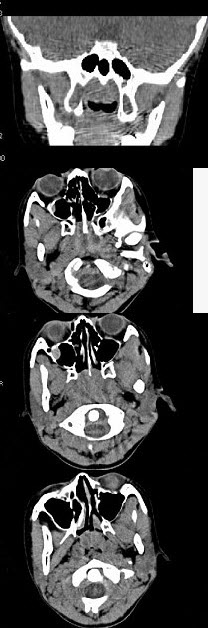

女,8岁,头痛,鼻塞半年余,CT如图所示,最可能诊断为()。

A、鼻咽癌

B、鼻咽部炎症

C、腺样体肥大

D、神经纤维瘤

E、咽后脓肿

C